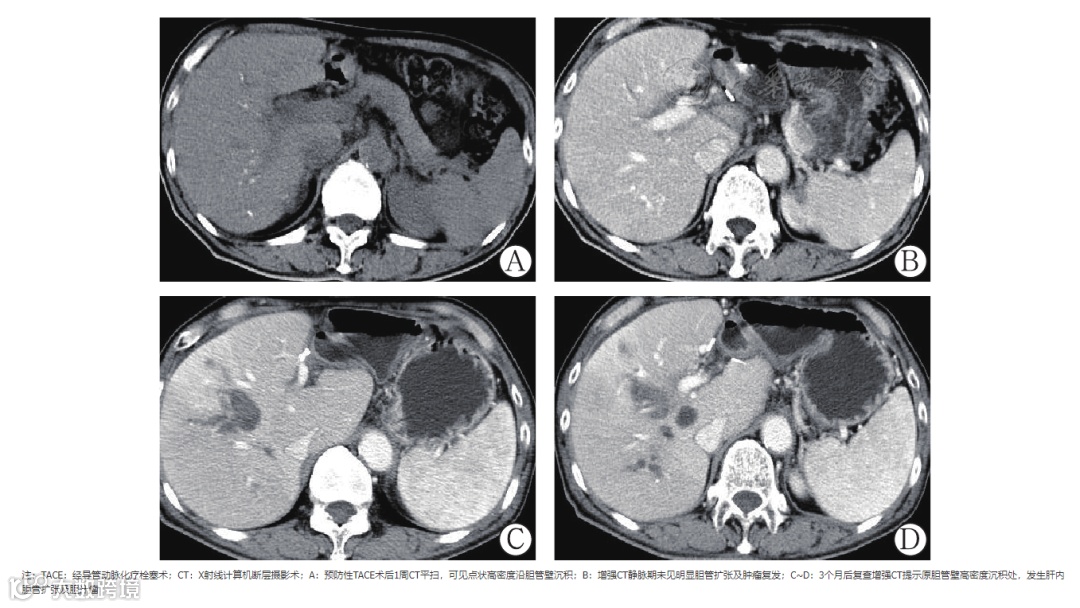

483例患者中,21例患者出现肝内胆管扩张、胆汁瘤及肝门部胆管狭窄等1种或多种影像表现,其中14.3%(3/21)患者首次TACE术后1周CT平扫出现线条样高密度影分布于胆管走行区,随访3个月后出现肝内胆管扩张及胆汁瘤(图2),与非胆管损伤组(1.1%,5/462)比较,差异有统计学意义(χ2=21.498,P<0.001)(表1)。本研究中大部分肝内胆管扩张的患者预后良好,无明显临床症状,后期随访无明显变化,其中9.5%(2/21)肝内胆管扩张的患者,随访中逐渐并发胆汁瘤的形成。另本研究中6例患者(28.6%,6/21)出现肝门部胆管狭窄,磁共振胰胆管造影(magnetic resonance cholangiopancreatography,MRCP)表现为肝门部胆管壁毛糙,其中4例经皮经肝胆道引流术(percutaneous transhepatic cholangial drainage,PTCD)治疗效果不佳,后期出现肝功能异常及反复胆道感染。

本研究发现21例胆管损伤患者中,有3例患者术后1周CT平扫显示胆管走行区线条样高密度影,后期出现肝内胆管扩张及胆汁瘤。我们推测胆管周围高密度影,可能是碘油沉积在胆管壁上,造成胆管周围血管网缺血损伤,引起胆管上皮细胞坏死,胆汁溢出,从而导致胆管及周围组织损伤等相关并发症。故作者认为1周后CT平扫胆管周围若出现线条样高密度影可能提示胆管早期损伤,此时应及时对症治疗,同时需避免胆管再次损伤的相关操作。Guiu等[16]认为实验室数据(主要是ALP)的早期变化,相比较于影像学表现,能更早预测胆管损伤,敏感性及特异性分别为60.3%、69.2%。我们研究发现TACE术后ALP持续升高的患者,后期易出现胆管损伤。本研究中21例胆管损伤患者,其中16例患者后期随访ALP均大于200 U/L,且持续3个月以上。故我们猜测ALP异常升高,可能提示胆管早期损伤,但其具体的分子机制及转化过程目前仍不明确,可作为今后进一步研究的方向。